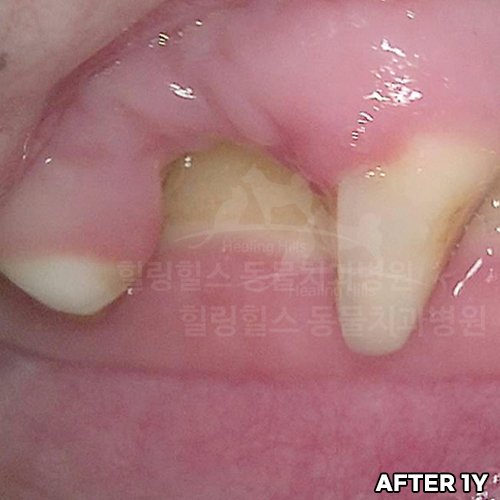

[자기치아살리기]

샘플

[최소침습적 발치 후 2주 경과]